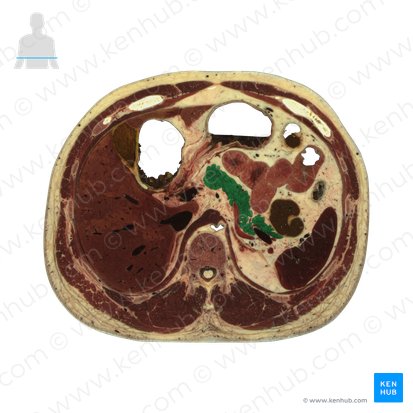

Le pancréas est un organe allongé d’environ 15 cm qui se trouve obliquement le long de la paroi abdominale postérieure, plus précisément au niveau des vertèbres L1 et L2. Dans un contexte clinique, sa position oblique rend impossible l’observation de l'ensemble de ses parties dans une seule coupe transversale. Le pancréas entre en contact avec plusieurs structures avoisinantes puisqu’'il traverse les régions épigastriques, l'hypochondre gauche, et une petite portion de la région ombilicale de l'abdomen.

À l'exception de la queue, le pancréas est situé dans l'espace rétropéritonéal de la cavité abdominale, c'est-à-dire derrière le péritoine. Si l'on cherche à illustrer l'emplacement de cet organe, un schéma du pancréas serait idéal pour mettre en évidence ces relations anatomiques, soulignant ainsi le rôle crucial du pancréas dans le fonctionnement de notre organisme.

Comme vous avez maintenant une meilleure compréhension de la localisation du pancréas, il est temps d'explorer son anatomie. Sur un schéma du pancréas, on remarque que cet organe parenchymateux est divisé en cinq parties anatomiques : la tête, le processus unciforme, l’isthme (col), le corps et la queue.